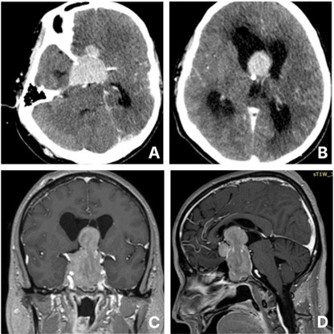

A 57-year-old male with no significant past medical history presented to the emergency department with a sudden onset of severe headache, vomiting, and progressive loss of consciousness. He was intubated for airway protection on arrival due to collapse. Initial CT imaging revealed a giant sellar lesion extending into the third ventricle, causing obstructive hydrocephalus (Figure 1). An emergent External Ventricular Drainage (EVD) was placed, and the patient was admitted to the Intensive Care Unit (ICU), where he was started on intravenous dexamethasone. Further systemic examination revealed an absence of body hair on the trunk and limbs, while facial and pubic hair remained intact. He exhibited no gynecomastia or galactorrhoea, and testicular volume was within normal limits. The family reported long-standing hair loss since adolescence, but had fathered four children by the age of 30. Laboratory investigations showed low levels of Follicle-Stimulating Hormone (FSH), Luteinizing Hormone (LH), testosterone, Growth Hormone (GH), and Free Thyroxine (FT4), with a normal Thyroid Stimulating Hormone (TSH) level and low Prolactin (PRL). He was started on levothyroxine for presumed central hypothyroidism.

MRI confirmed the presence of a giant sellar lesion extending into the suprasellar region and 3rd ventricle to the foramen of Monro (Figure 1). The lesion exhibited enhancement and diffusion restriction on Susceptibility-Weighted Imaging (SWI), with invasion of the bilateral cavernous sinuses and encasement of the internal carotid arteries. Also, the optic chiasm was compressed. In reduced sedation attempts, the patient was decerebrating.